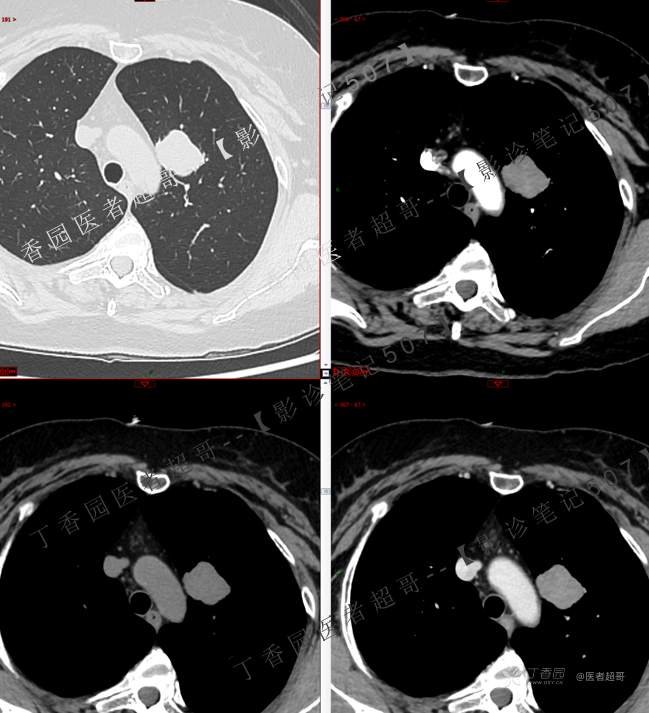

患者性别:女

患者年龄:50岁

简要病史:患者4月余前出现无明显诱因及病因出现胸痛,无咳嗽咳痰等表现。

小细胞肺癌 (54)